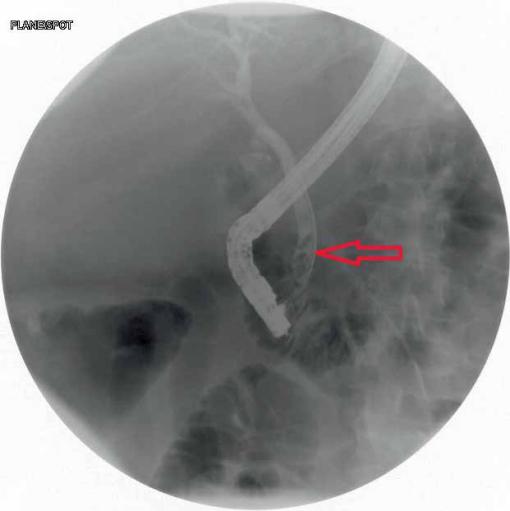

一名49岁的女性患者因上腹部疼痛伴恶性呕吐于当地医院急诊科就诊,两个月前患者因胆石症,胆总管扩张,梗阻性黄疸行内镜逆行行胰胆管造影术,,取出3块胆石,如图1、2。行腹部CT检查,提示小肠梗阻,胆石性肠梗阻,十二指肠瘘,如图3、4。患者立即行急诊手术治疗,术中发现扩张小肠有明显胆石阻塞及压迫痕迹,取出胆石,由于小肠压力过大,出现部分坏死,因此行小肠部分切除术,如图5。在距离回盲部60cm小肠处取出大小约3.5cm*3.5cm胆结石,如图3。用腹腔镜从Treitz韧带检查小肠,并未发现有残余结石,病人在手术后已康复,顺利出院。

图1 ERCP提示胆总管内可见多个结石